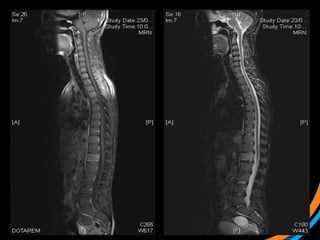

Case study 3(Patient 009) • 44, Female, ECOG 1 • RCC diagnosed 2007. Metastatic recurrence in 2012 • Prior RT to prevascular LN 50Gy/20# (2012) • Started on Pazopanib, then everolimus • Recent MRI spine shows met involving T3 and L1 vertebral body, with involvement of superior endplate (L1)  1) Review the images  2) Target the lesion

• 40.

• 41.

• 43.